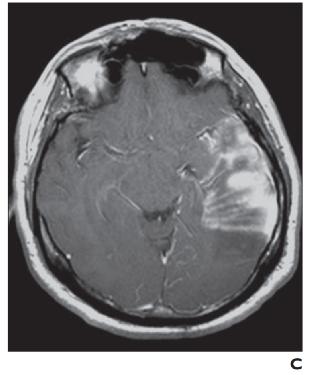

MRI 也可用于急性卒中,尽管技术和人员要求限制了它在许多中心的应用。DWI 是检测超急性梗塞(出现后 < 30 分钟)最敏感的序列,先于 CT(6 小时)和 T2 加权成像(6-12 小时)识别病情变化。急性梗塞中的扩散受限分别对应于 DWI 和 ADC 图上信号增加和减少的区域。随着梗死发展为亚急性和慢性阶段,会发展为血管源性水肿和脑软化症。这反映在 T2/FLAIR 信号强度的逐渐增加,且伴随着扩散系数的正常化(图3A ), 3B, 和3C)。也可以进行3D-TOF MRA或者3D-ASL检查。然而,与 CT 相比,空间分辨率较差,图像容易出现运动、磁化率和流动伪影。

图 3A —患有线粒体脑肌病、乳酸性酸中毒和中风样发作 (MELAS) 的梗死患者的 MR 图像。T2 加权图像显示两个枕叶信号增加,右侧(粗箭头)大于左侧(细箭头)。

图 3B —患有线粒体脑肌病、乳酸性酸中毒和中风样发作 (MELAS) 的梗死患者的 MR 图像。弥散加权图像也显示双侧高信号,右侧(粗箭头)大于左侧(细箭头)。

图 3C —患有线粒体脑肌病、乳酸性酸中毒和中风样发作 (MELAS) 的梗死患者的 MR 图像。表观扩散系数图像(ADC)显示右侧信号减弱(粗箭头)但左侧信号正常(细箭头)。因此,右侧病变为急性梗死,弥散受限。左侧病变代表亚急性或慢性梗塞,弥散加权图像上有 T2 透过效应。